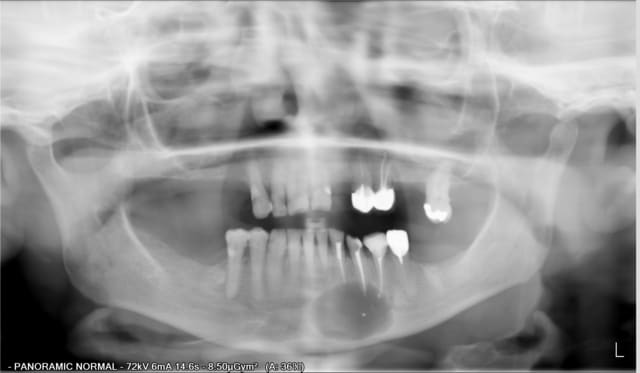

Petit cas qui permet de sortir de l'ordinaire.

Exérése d'un Kyste d'origine dentaire aprés avoir repris les endo sur 32/33/34.

Comblement avec du B-TCP et membrane vicryl.

- pour le V3, j'avais fait un scanner,la corticale était refoulé et le kyste était sans contact direct avec le canal.

- kyste asymptomatique de découverte fortuite.